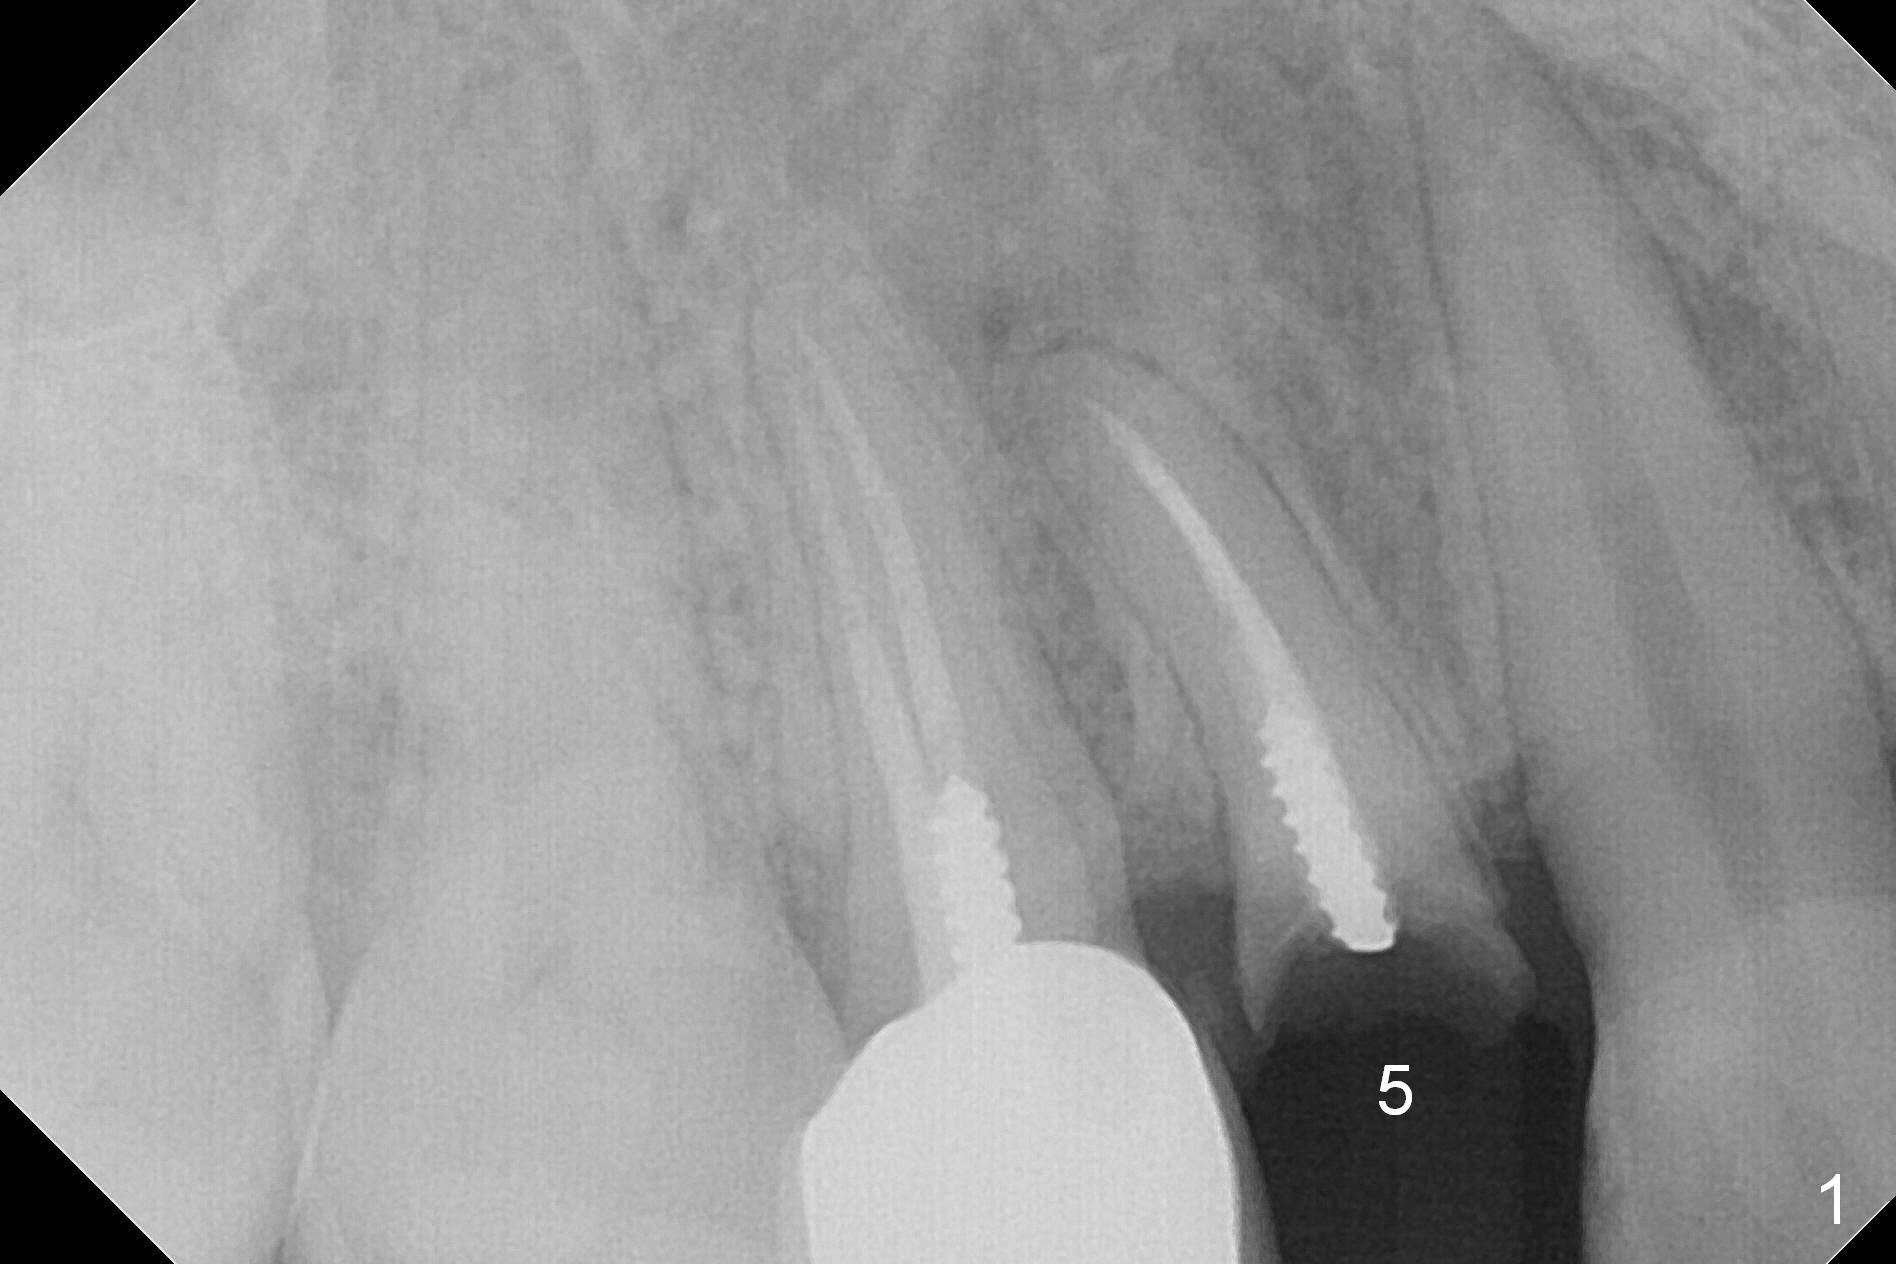

A 34-year-old man (smoker, half a pack a day) has residual root at #5 (Fig.1) with large periapical radiolucency (Fig.2 red dashed line). Since the root curves distally (Fig.3 black area, Clindamycin), osteotomy will be established in the mesial wall (red long arrow). A 3.8x16 or 18 mm implant is to be placed for primary stability (Fig.4). To reduce periimplantitis associated with smoking, place the implant deep. The implant appears to have better surface treatment. Pack sufficient bone graft and membrane. Immediate provisional should have good seal. To place the implant deep, osteotomy will be attempted with a long 1.5 mm pilot drill (PA), followed by 2 mm one with extension and 3.0x18 mm drill.